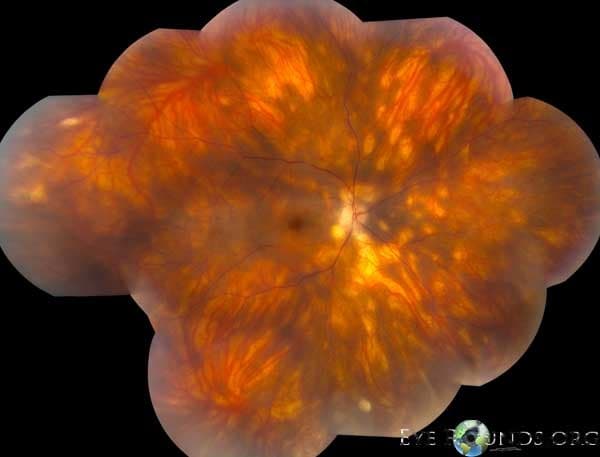

Clinical Images

High-resolution clinical photographs showing various presentations of anterior uveitis (iritis/iridocyclitis).